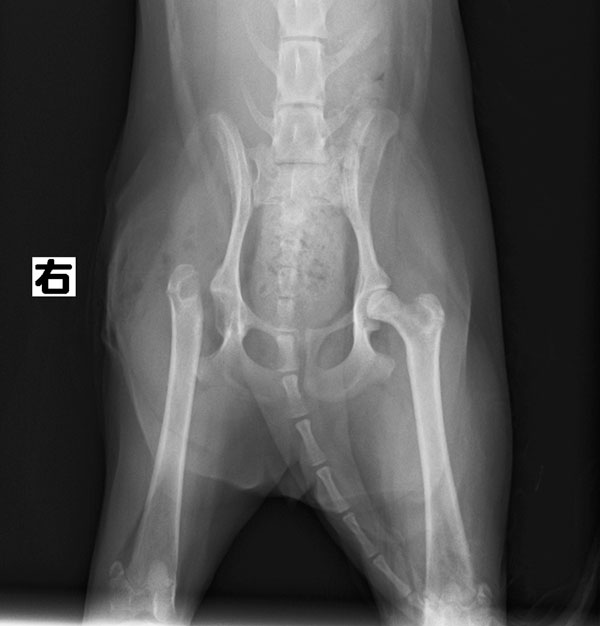

手術紹介

大腿骨頭切除